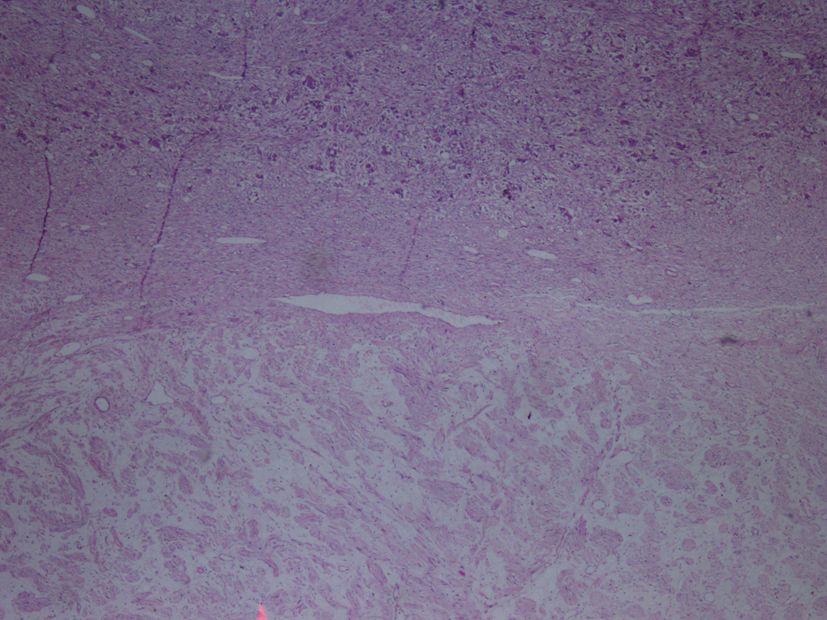

Macroscopic examination of the radical nephrectomy material measuring 18 × 7 × 5 cm showed a solid, gray-white colored tumor measuring 10 × 7 × 3 cm, located in the upper pole of the kidney but without any direct relation to the kidney. Focal adrenal tissue was observed in the cross-section of the tumor. The kidney and surgical margins were tumor-free. Three lymph nodes measuring 1 cm in diameter were detected in the renal hilus. The microscopic examination revealed mature ganglion cells in Schwannian stroma. The immunohistochemical examination showed strong positive staining for S100, neuron-specific enolase, synaptophysin and chromogranin. These three lymph nodes are considered to be reactive lymph nodes (Fig. 1-3).

![]() Click for large image | Figure 1. Hematoxylin-eosin staining demostrating H&E (× 40). |

![]() Click for large image | Figure 2. Hematoxylin-eosin staining demostrating H&E (× 100). |